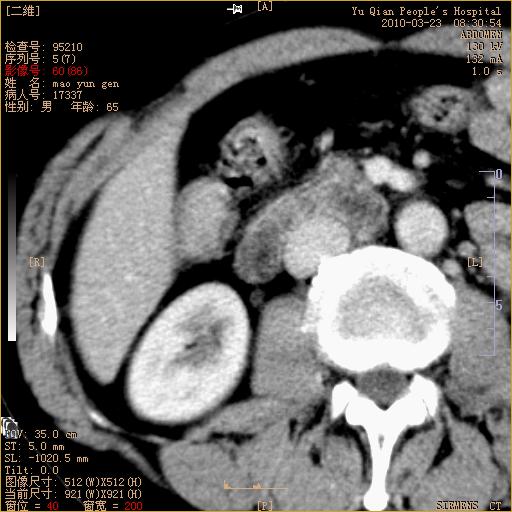

标题: CT25266:消瘦月余,前来肝部检查,请看看肠腔 [打印本页]

标题: CT25266:消瘦月余,前来肝部检查,请看看肠腔

升结肠肠壁增厚,不均强化,考虑升结肠腺癌可能性,建议肠镜检查。

1)考虑升结肠癌。2)右肾小囊肿。